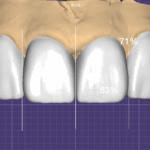

사진 3은 지르코니아 크라운 제작을 위해서 중간 과정으로 베이스가 되는 캡을 맞춰보는 과정입니다.

이중 검증 프로토콜(Dual verification protocol):

첫 번째 검증 – 색상 차폐(Color masking verification): 치아의 색이 효과적으로 차단되는지 확인합니다. 베이스 캡을 지대치에 시적하여 어두운 치아 색이 투과되지 않는지 확인합니다. 만약 색상 차단이 불충분하면 베이스 두께를 증가시키거나 불투명도를 높입니다.

두 번째 검증 – 변연 적합도(Marginal fit verification): 치아와 잘 맞는지 확인합니다. 변연 적합도(Marginal fit), 내면 적합도(Internal fit), 접촉점(Contact point) 등을 정밀하게 검증합니다.

이 **베이스 캡 시적(Base cap try-in)**은 최종 결과의 성공을 보장하는 핵심 단계입니다. 베이스가 확정된 후, 그 위에 심미적 도재(Esthetic porcelain)를 적층하여 최종 크라운을 완성합니다.